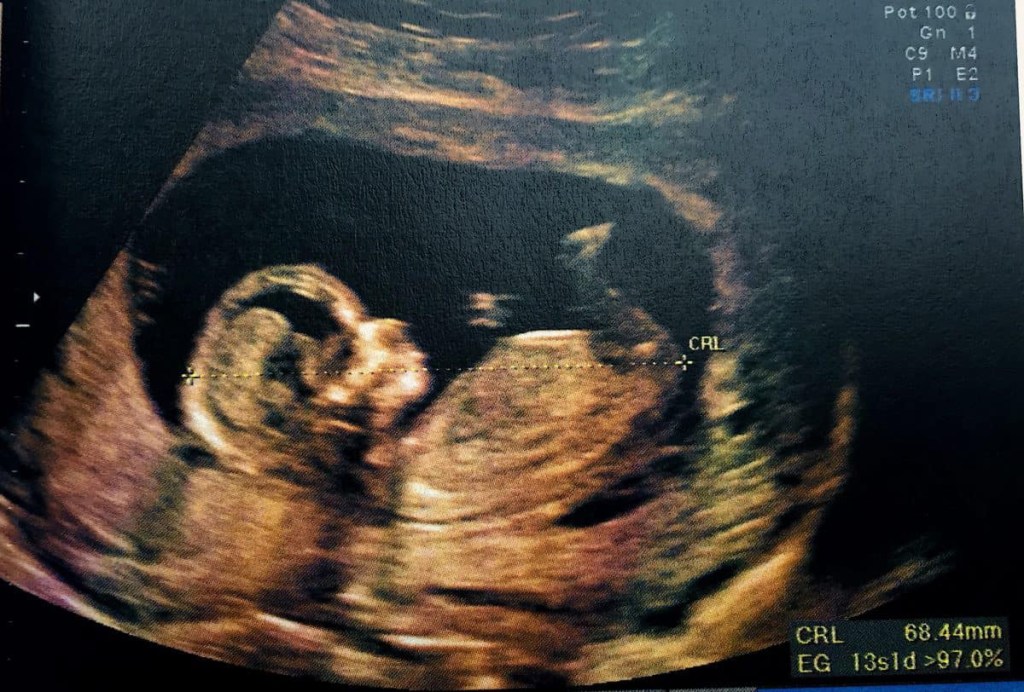

O pequeno corpo estava enrolado sobre si próprio, confortável no escuro do ventre materno. Escuta com atenção os sons que ouve, em especial uma voz que sobressai. A ternura do timbre da voz da mãe deixa-lhe uma marca profunda, um verdadeiro contrato de amor.

Hoje é o dia mais importante da vida do pequeno ser cujo espírito habito. Agita-se no útero materno. Pressente que está na hora. Mesmo assim, a primeira contração atinge-o de surpresa. Sente a pressão que o expulsa. A ansiedade aumenta. O pequeno coração acelera. Parece que lhe sai do peito. Não tenta compreender o que se passa. Confia na natureza. Sabe que faz parte dela.

A segunda contração é mais forte. Sente o sofrimento da mãe. Neste momento, são um, partilhando do mesmo corpo.

Já assisti a milhares de lutas como esta. A Morte assiste também, torcendo, tal como eu, para que a criança sobreviva, porque nada há de mais triste do que uma vida que não acontece. É assim desde sempre. a dualidade eterna da morte e da vida. Os extremos que apenas se encontram no momento do nascimento, e isso diz tudo da importância da tremenda luta que a mãe e o filho partilham.

A nova contração faz a mãe berrar. O bebé ouve. Também quer gritar. A dor é partilhada. Dizem que as mães devem ter dores no parto para que os bebés não as tenham. Eu, que vivi milhares de nascimentos, sei que isso é uma mentira: a dor da mãe é a dor do bebé, e vice-versa.

Ouvem-se as vozes aflitas dos médicos e enfermeiros. Sinto nas suas almas uma ansiedade crescente que se transforma num medo contido. São, acima de tudo, profissionais que não podem levar para casa as dores alheias. Por mais empatia que tenha a alma, sentir em excesso a dor dos outros pode destruir a pessoa. Há limites e estes profissionais sabem disso. Hoje é apenas mais um exemplo, uma mãe que luta pelo filho. Um filho que luta pela vida.

Já exausta, a mãe arranja forças de onde pode para expulsar aquele que amou durante nove meses. O parto é um ato de amor violento, como todas as separações. A vida tem um preço elevado.

O bebé é tirado com a ajuda de ferros. Os médicos pegam nele, observam-no. Vejo nas suas almas a apreensão dos seus espíritos – são minhas velhas conhecidas, mas o momento não é de socializar.

A criança não respira.

No último instante, o milagre acontece: primeiro, o bebé, dois quilos de gente de pele arroxeada pelo esforço, começa por respirar de forma irregular, depois irrompe num choro incessante, que é a forma como os humanos anunciam a sua chegada.

Comentário: um conto diferente, no qual a alma (ou atman, aqui atuando no papel de “espírito guardião”) é o narrador de uma criança ainda no ventre da mãe. Dissociada do corpo ou mesmo do espírito desse ser (uma das muitas digressões filosóficas/ontológicas ao longo do texto), essa consciência reflete sobre a questão da existência e narra o processo traumático de um nascimento complicado, com fórceps e parada respiratória.